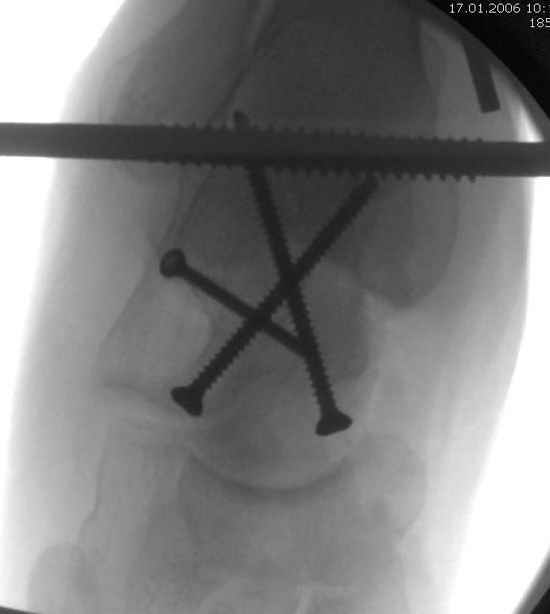

Из-за отека на стопе тактика лечения у всех была

одинаковая: временная наружная фиксация до спадения отека, при изолированных переломах они выписывались домой и через дней 7 госпитализировались на оперативное лечение.

Примеры на снимке...